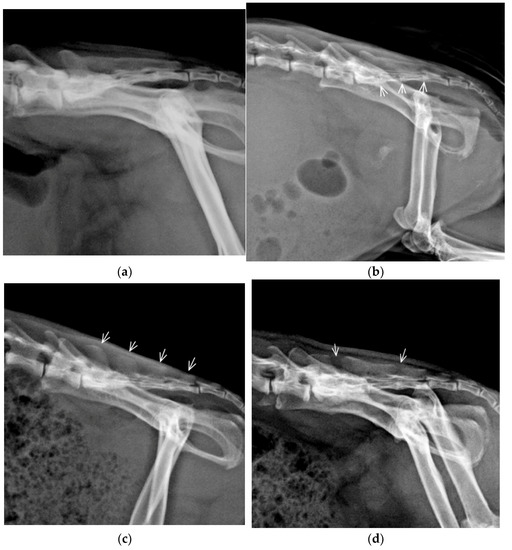

3.2. Congenital Vertebral Anomalies

| LTV | Asymmetrical | LS junction | C7/Th13/L5+LTV/S4/Cd6 | 1 | 2.08 | 16.67 | F |

| LS junction | C7/Th13/L5+LTV/S3/Cd6 | 1 | M | ||||

| LS junction | C7/Th13/L5+LTV/S4/Cd5 | 1 | F | ||||

| LS junction | C7/Th13/L5+LTV/S4/Cd6 | 1 | F | ||||

| LS junction | C7/Th13/L6+LTV/S3/Cd5 | 1 | M | ||||

| TTV, LTV | Bilateral rudimentary rib, asymmetrical LTV | TL, LS junction | C7/Th12+TTV/L5+LTV/S4/Cd5 | 1 | 0.42 | 3.33 | F |